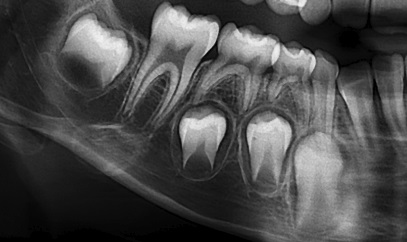

Se presenta la radiografía panorámica (2016) de una paciente femenina de 7 años de edad con un defecto de RIPE en el germen de la pieza 44, de localización distal y profundidad menor a ⅓ de la altura dentinaria (grado I) (figura 2). En la THC adquirida en 2022, con un tamaño de vóxel de 0,15 mm, se observó un defecto hipodenso en forma de fosa, localizado en el esmalte y la dentina (grado I) del tercio medio de la superficie distolingual (figura 3).

Se muestra la radiografía panorámica de una paciente femenina de 8 años de edad. Se observa la presencia de un defecto de RIPE en el germen dentario de la pieza 44, localización mesial y profundidad dentinal de grado I (figura 4). En la THC adquirida, con un tamaño de vóxel de 0,15 mm, se observó un defecto hipodenso de esmalte y dentina (grado I) ubicado en la vertiente mesial de la cúspide lingual (figura 5).